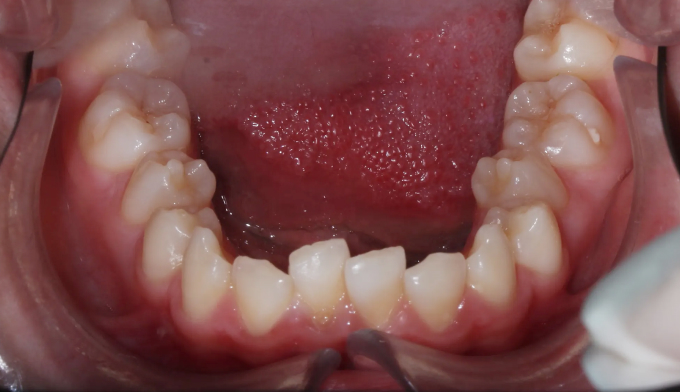

위 작은어금니가 겹쳐져서 맹출하였습니다.

유치를 발치할때 잘못된 순서로 발치하게 되는 경우 이런 경우가 발생할 수 있습니다.

유치 발치 후 영구치가 맹출할 공간을 확보해주어야 위와 같은 일이 생기지 않습니다.